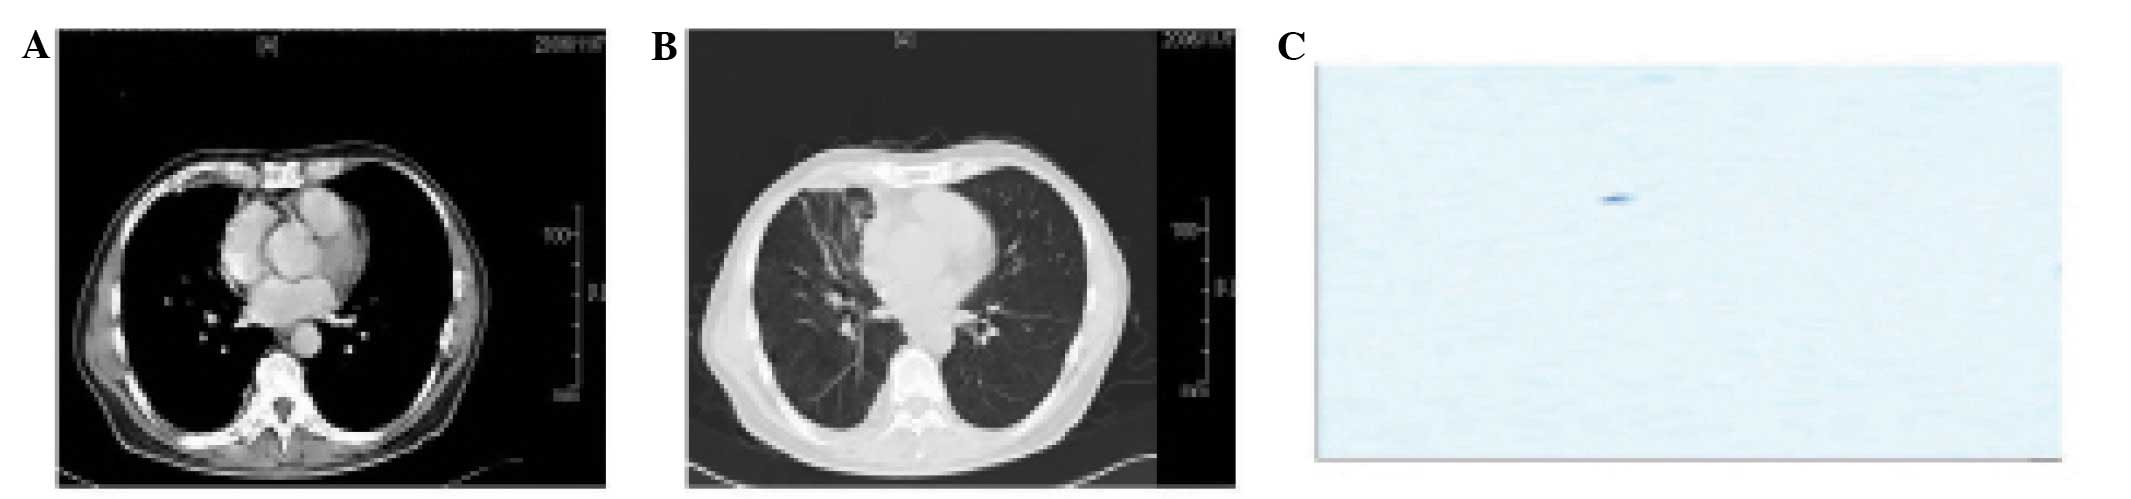

admission, the patient began to develop a severe headache with

nausea and vomiting but without cranial and spinal nerve

dysfunction, or signs of leptomeningeal irritation, such as

Brudzinski’s or Kernig’s sign. There were no abnormal signs in the

head magnetic resonance (MR; Fig. 2A

and B) or gastroscopy images. In the first week, a lumbar

puncture was performed and the pressure of the CSF was 18 cm

H2O. The result of the test was colorless, positive for

protein, had a total cell number of 10×106/l and

contained cancer cells (Fig. 2C)

(4). Chemotherapy was started with

3) and 9 (cycle 4). In week 12, the pressure of the CSF was 12 cm

H2O. The CSF analysis was colorless, positive for

protein, had a total cell number of 0/l and contained no cancer

cells (Fig. 3C). The CT showed that

the shadow in the right lower lung was 0.5×0.5 cm and that the

pleura of the right chest was thickened (Fig. 3A and B). Another 4 cycles of